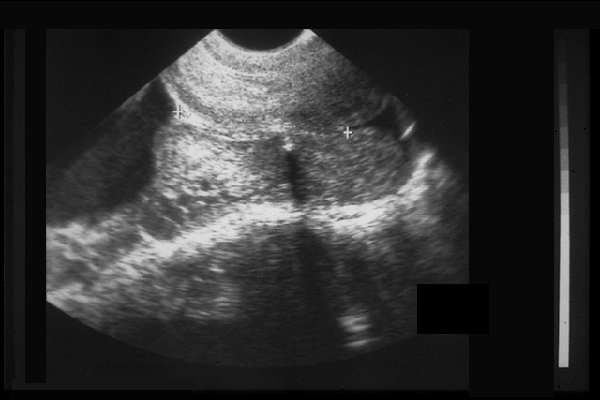

Col avec cerclage.